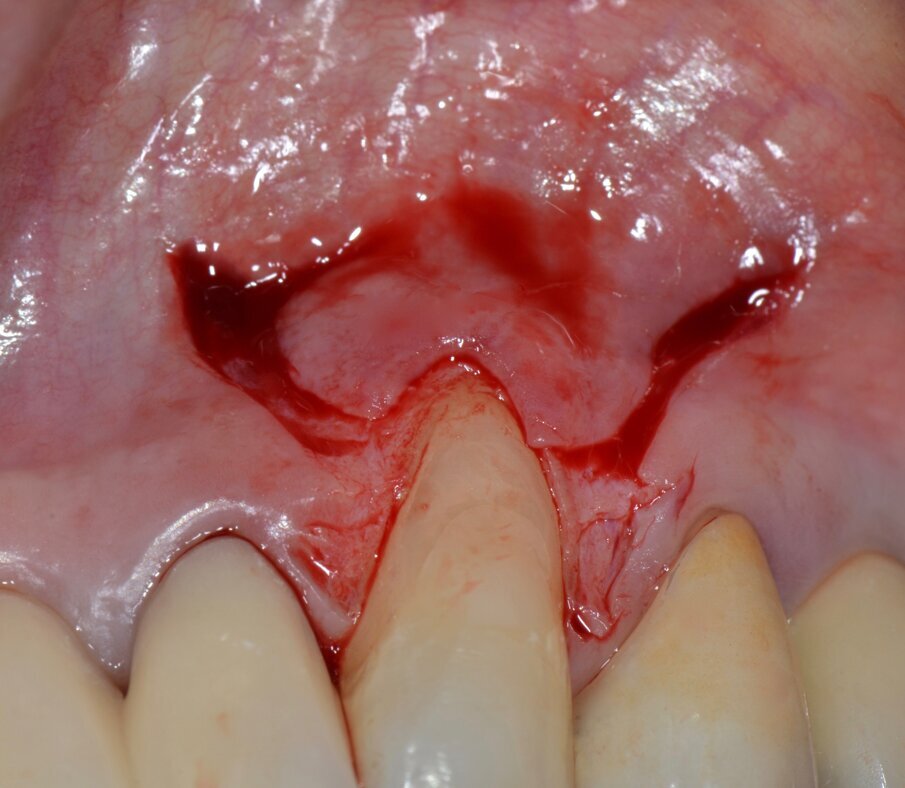

Dopo circa un mese viene eseguito un lembo a scorrimento coronale con innesto di tessuto connettivo (CAF+CTG) prelevato dal palato con la “Tecnica di Langer e Langer mod. J.Bruno” per coprire la recessione sul canino superiore sinistro e ispessire il tessuto sopra il quale verrà posizionata una faccetta in ceramica (Figg. 12-17). A due mesi dal CAF+CTG si può notare la maturazione dell’innesto con un ottimale spessore mantenuto e lo spazio guadagnato sul canino controlaterale con la ORS (Figg. 18, 19).